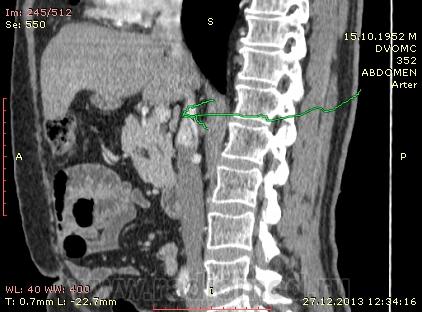

61 год. Рак желудка, в 2011 году субтотальная резекция. Жалоб нет. На вид здоровый, не худой, розоволицый мужик. На УЗИ нашли гиперэхогенное образование в VI сегменте печени 0.8 х 0.6 см. Рекомендовали КТ. Ну и вот: в печени в VI сегменте мелкий кальцинат...больше ничего страшного не вижу. В аорте куча мягких и "твердых" бляшек. Очень интересует Ваше мнение по поводу найденых, как мне кажется, достаточно крупных лимфоузлов...не похожи на метастатическое поражение?

Похоже еще и люмбализация S1 со спондилелизом и антелистезом?

Желудок резецирован по Б-II, лимфоузлы не увеличены. Подпеченочный аппендикс.

и в портальную фазу практически равны по плотности сосудам. Нормальные лимфоузлы всегда гиподенснее сосудов. Форма лимфоузлов может быть любой, и лишь округлость во всех реконструкциях может свидетельствовать о лимфаденопатии. Обычно паракавальный узел крупный и овально-округлый в короналах, но уплощенный на сагитталах, как в вашем случае - нормальный. Не всегда видны жировые ворота лимфоузла. При воспалительной лимфаденопатии узел может быть крупным, "набухшим", при сохранении жировых ворот. Округлый лимфоузел размерами даже меньше нормы в коротком поперечнике, но с патологическим накоплением контраста, считается измененным, и подозрителен на метастаз.

Для информации: симуляция паракавальной лимфаденопатии: